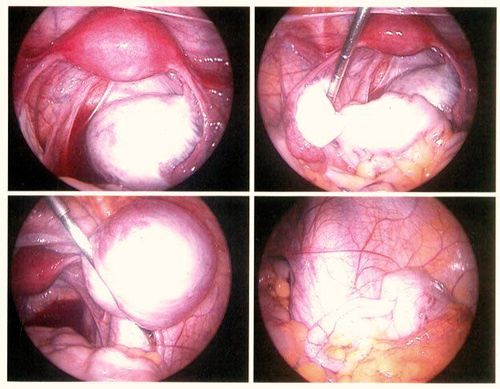

- Nội soi ổ bụng: Phương pháp này cho phép các bác sĩ chẩn đoán và điều trị lạc nội mạc tử cung bằng cách sử dụng một dụng cụ có gắn máy quay phim. Bác sĩ đưa dụng cụ có đèn chiếu sáng vào cơ thể bệnh nhân, cùng với một ống kính để quan sát bên trong vùng xương chậu và tìm ra lạc nội mạc tử cung. Hình ảnh thu được giúp bác sĩ xác định tình trạng bệnh, mức độ tổn thương, và vị trí tổn thương để đưa ra phương án điều trị thích hợp.

- Chẩn đoán bằng nội soi: Trong quá trình này, bác sĩ bơm khí vào ổ bụng và rạch một vết nhỏ để nội soi. Qua ống nội soi, bác sĩ có thể quan sát toàn bộ ổ bụng. Đây là cách chẩn đoán tình trạng lạc nội mạc tử cung đáng tin cậy nhất. Bác sĩ có thể lấy mẫu mô nhỏ để kiểm tra xem có tế bào ung thư hay không. Trong suốt quá trình thực hiện, bác sĩ sẽ gây mê toàn thân cho bệnh nhân.

- Phẫu thuật nội soi: Nếu phát hiện có dấu hiệu lạc nội mạc tử cung, bác sĩ sẽ tiến hành phẫu thuật loại bỏ các mô lạc nội mạc tử cung khi nội soi. Các khối u được cắt bỏ, đốt bằng laser hoặc các kỹ thuật khác.